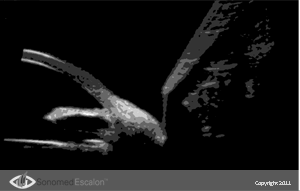

?сследование при помощи VuMAX® функций проходимости в случаях трабекулэктомии и конъюнктивальном химозе, можно оценить успешность и эффективность проведенных пост-оперативных вмешательств таких, как фильтрующая хирургия. Кроме того, VuMAX® обеспечивает четкую визуализацию Шлеммова канала, что необходимо в случаях проведения вискоканалостомии.

Приложение Pro 2000 Шлеммов канал после операции